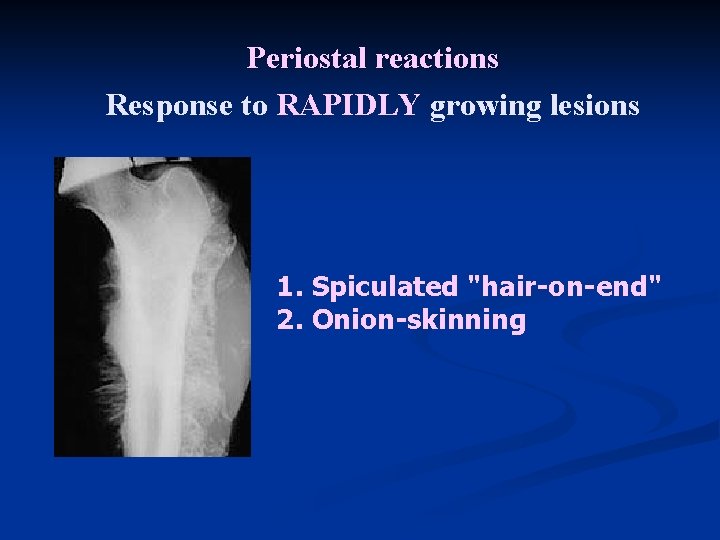

Periostal reactions Response to RAPIDLY growing lesions 1. Spiculated "hair-on-end" 2. Onion-skinning

n Codman's triangle

Periostal reactions Response to SLOW growing lesions focal cortical thickening

n n n Radiology of a long bone usually show a large, ill-defined tumor. The bone-producing (osteoblastic) lesion is located in the medulla near the metaphysis Lifts up the periosteum (periostal reaction) n n n often producing "Codman's triangle", an angle between the outer cortex and the elevated periosteum, Sun-rays pattern Less common : n destructive (osteolytic) lesions with a "moth eaten" appearance of the cortex.

n Ewing's sarcoma may occur in any bone but most frequently involves long bones. n n Femur (27%), pelvic bones (18%), tibia and fibula (17%), humerus (10%), scapula (6%). Radiology: A mottled "moth eaten" destructive lesion in the diaphysis n periosteal reactive new bone n n sometimes formed in concentric layers and producing an "onion skin" appearance, and often accompanied by a soft-tissue mass.